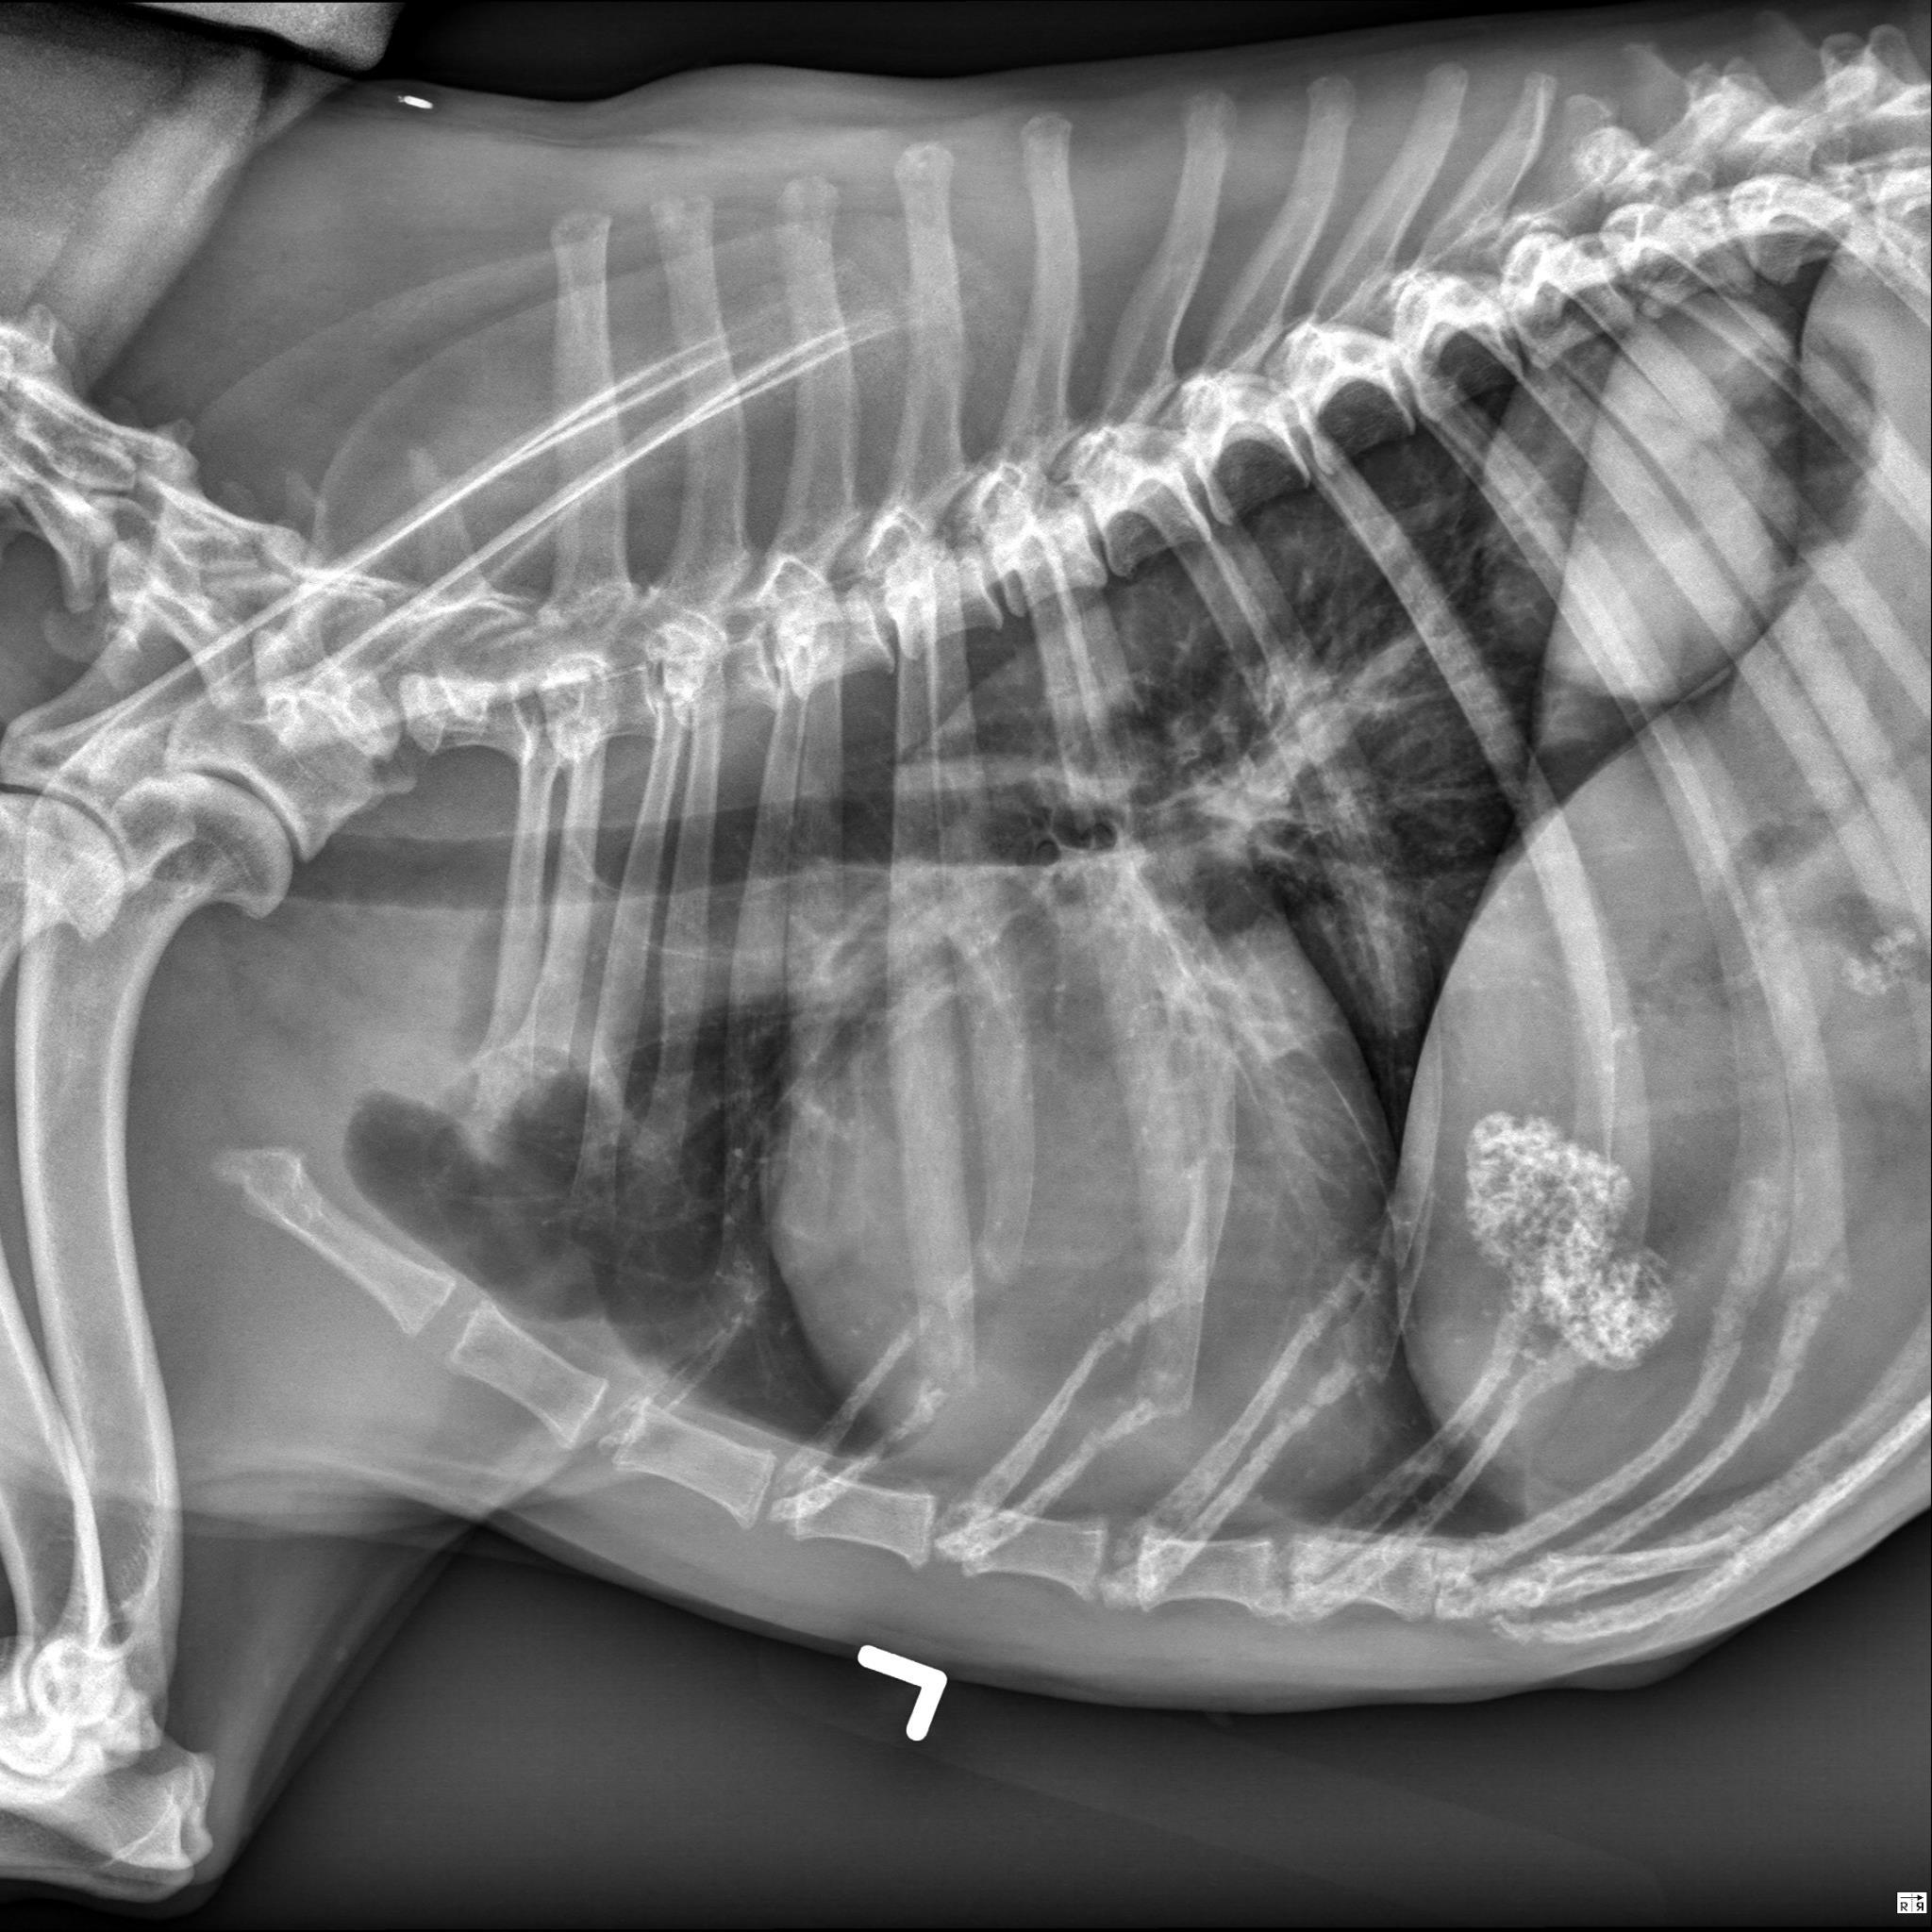

Thorax, 3 views:

There is an oval, well-circumscribed, soft tissue opaque mass associated with the most caudal dorsal aspect of the right caudal lung lobe. This mass measures approximately 7.0 x 7.0 x 6.6 cm (length X height X width) based on the left lateral and VD views (without correction for magnification).

There are additional multifocal pinpoint mineral opaque foci throughout the lung fields, consistent with incidental pulmonary osteomata.

An additional faint curvilinear soft tissue opacity is superimposed with the cranial dorsal thorax from the 1st-2nd pair of ribs on both lateral views, consistent with incidental plate like atelectasis.

The cardiovascular structures, mediastinal structures, pleural space, diaphragm, and thoracic wall are normal. There is incidental caudal thoracic spondylosis deformans.

There are sharply marginated but irregularly shaped regions of heterogeneous mineral opacity superimposed with the right cranial aspect of the liver as well as the right cranial abdomen (superimposed with the expected location of the proximal descending duodenum on the lateral views and visible in the plane of the right 11th intercostal space on the VD view).

On both lateral views, there are faint branching gas opacities superimposed with the cranial abdomen which appear to be located within the hepatic parenchyma.

Single large right caudal lobar pulmonary mass. A primary lung tumor (pulmonary carcinoma) is most likely. No evidence of pulmonary metastatic disease.

Granular mineral opacities in the plane of the right cranial abdomen are most consistent with mineralization within the gallbladder and common bile duct. Dystrophic mineralization of hepatic parenchyma, pancreas, and/or regional abdominal fat are considered as alternate but less likely etiologies. The branching gas opacities in the plane of the liver are likely associated with the intrahepatic bile ducts.